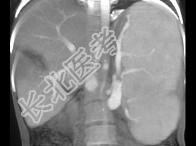

- 单项选择题患者肝移植术后1月,结合图像, 最可能的诊断为 ( )

A、肝脓肿

B、正常术后表现

C、肝梗死

D、血肿

E、以上都不是